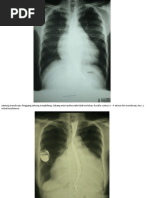

EFUSI PLEURA

Cor tidak membesar.

Sinus dan diafragma kanan/kiri berselubung. Sinus dan diafragma

kiri/kanan normal.

Pulmo:

- Hili normal.

- Corakan bronkovaskuler normal.

- Tampak perselubungan opak homogen di hemitorak bawah

kanan/kiri

KESAN :

- Efusi pleura kanan/kiri.

- Tidak tampak kardiomegali.